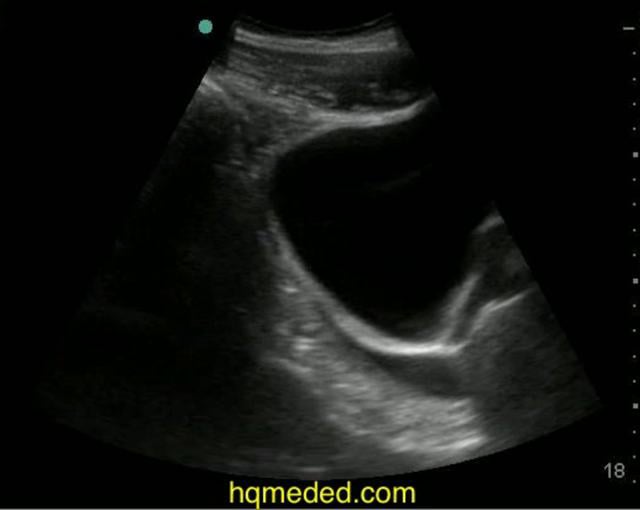

From ultrasound.guide

Pelvic Ultrasound Pelvic Free Fluid Treatment For Free Fluid In Pelvis In some cases, no treatment may be necessary, as the fluid may. Treatment for free fluid in the pelvis depends on the cause. However, for pathological causes, treatment varies based on the underlying condition. Infections may be treated with antibiotics. Identifying the symptoms associated with free fluid in the cul de sac is essential for early diagnosis and treatment. Some. Treatment For Free Fluid In Pelvis.